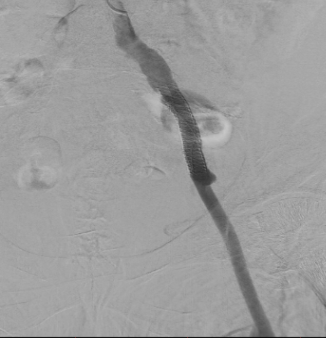

Через подвздошно-бедренный шунт, установлен интродьюсер (порт служащий для заведения в сосуд хирургического инструментария), далее по рентген контролем позиционирован и имплантирован стент в подвздошную артерию с переходом на ранее установленный шунт.

Ангиографическая картина перед стентированием

Ангиографическая картина после стентирования